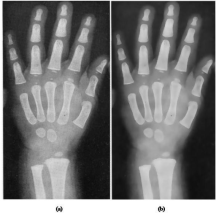

Ni siquiera

las falanges de mis dedos

podrán sostener un lápiz

_____________ para escribir

_

lo que están viendo.